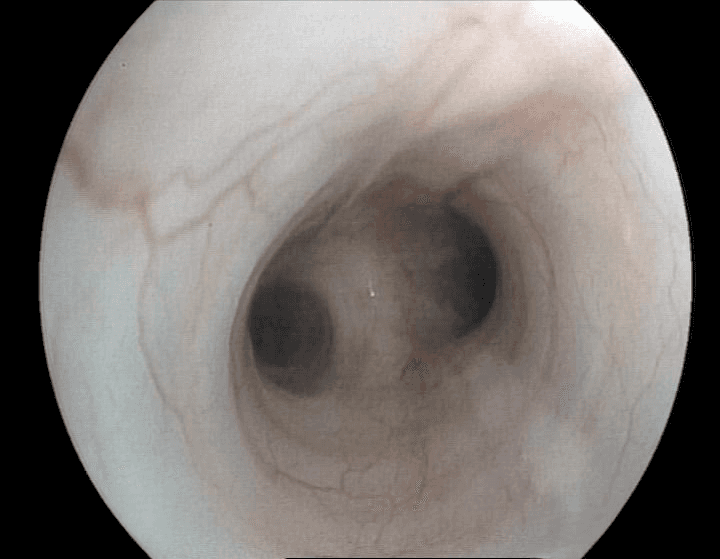

Endoscopie Interventionnelle

Colonne d'Endoscopie